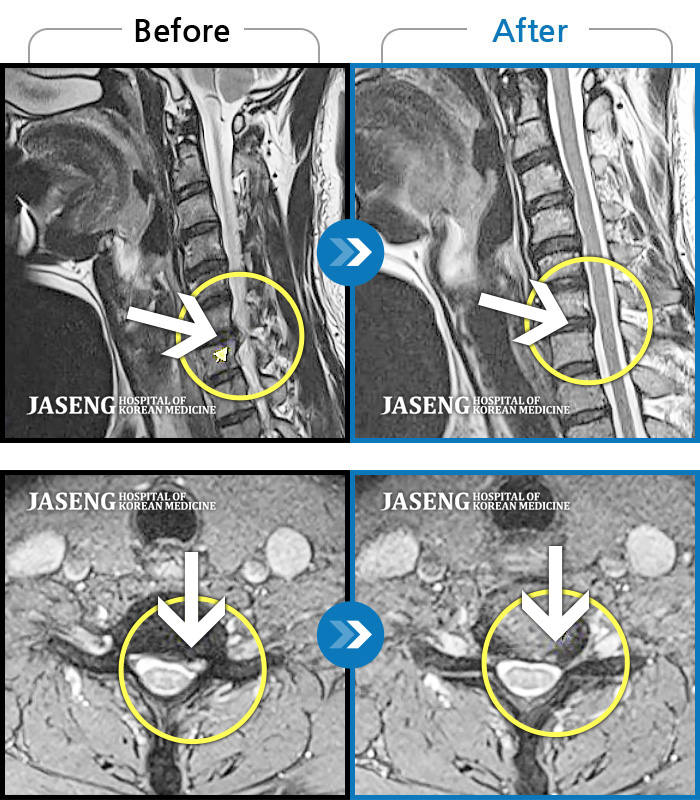

자생 비수술 한방통합치료 후

터진디스크가 흡수된 모습

우측 후경부부터 견갑골내연까지 통증, 우측 팔에서 손가락까지 이어지는 저림감

2023.07.08 ~ 2023.11.07